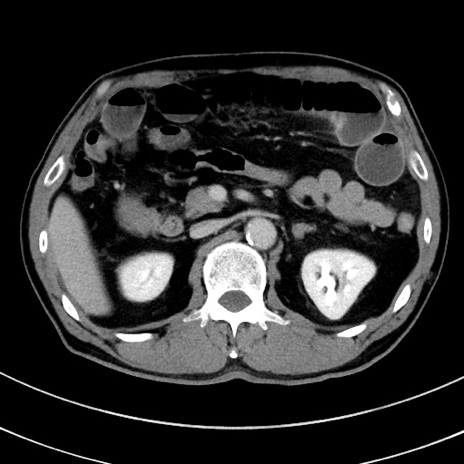

冠状断像

【症例】 60歳代男性

【主訴】 黒色吐物

【現病歴】 4日前から嘔気自覚、2日前の朝食後にも嘔気あり、自分で手で嘔吐反射起こし嘔吐したところ血が混ざっていたため受診。

【既往歴】 5年前汎発性腹膜炎を伴う急性虫垂炎で手術、高血圧、前立腺肥大症、高脂血症

【身体所見】 腹部正中に手術癩痕あり 腹部平坦・軟圧痛なし膨満感あり

【データ】WBC 8400、CRP 4.54